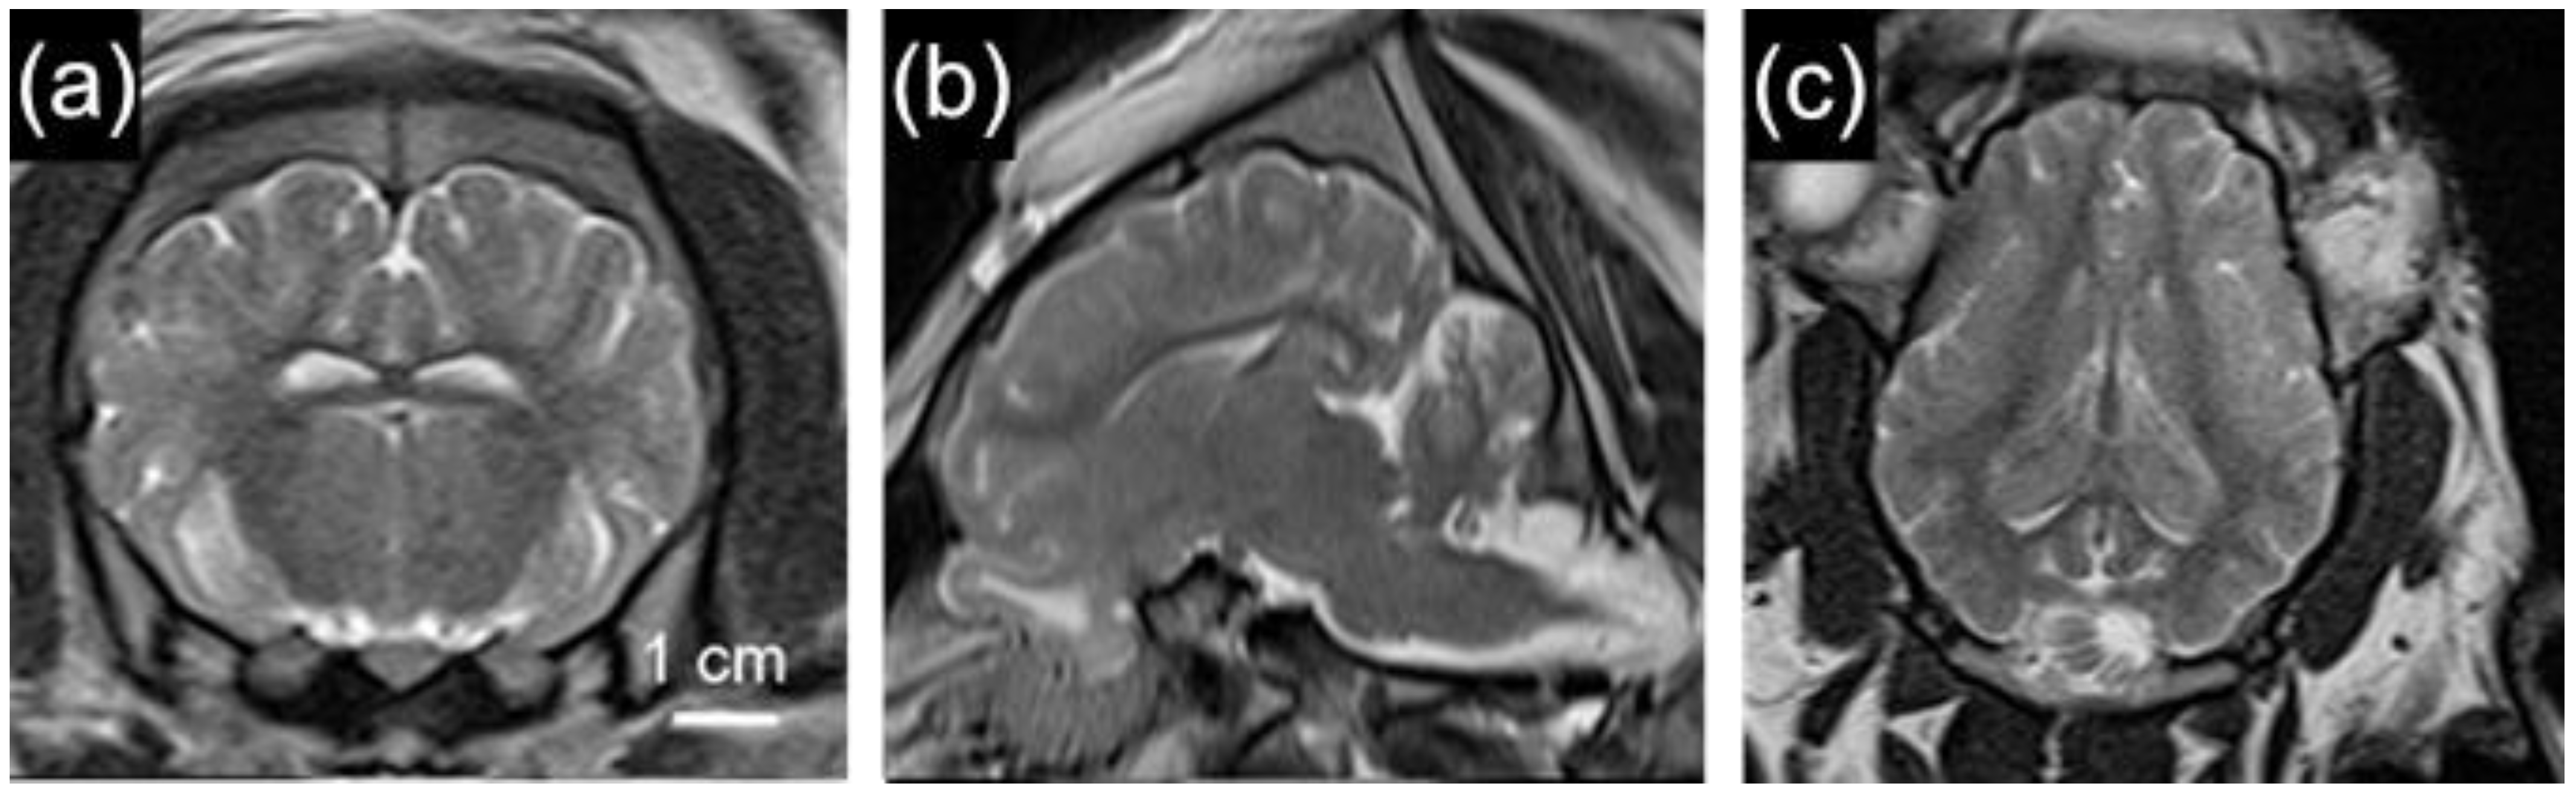

2.3. Similarities of the Pig Brain

2.5.2. Neuroimaging